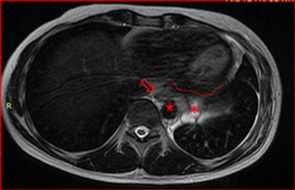

After the surgery, evaluation images in February, 2021 showed residual mass close to the descending aorta, the distal esophagus and the pericardial leaflet (Figure 2).

Figure 2: After R1 surgery, a possible residual mass (asterisk)-3.5 cm in its greatest dimension is seen on posterior mediastinal fat, close to the descending aorta (star), esophagus (empty arrow) and the pericardium (line).

Right after the chemotherapy, he also received Stereotactic Body Radiation Therapy (SBRT) - 35 Grays in 5 sessions in June, 2021), as well as, to decrease the likelihood of disease increment. In vain, so the persistence of disease in contact with the pericardium, as showed in Figure 3, would progress shortly

Figure 3: Persistence of the tumor-3.0 cm in its greatest dimension, (arrow) on the posterior mediastinal fat after chemotherapy, close to the pericardium (line).